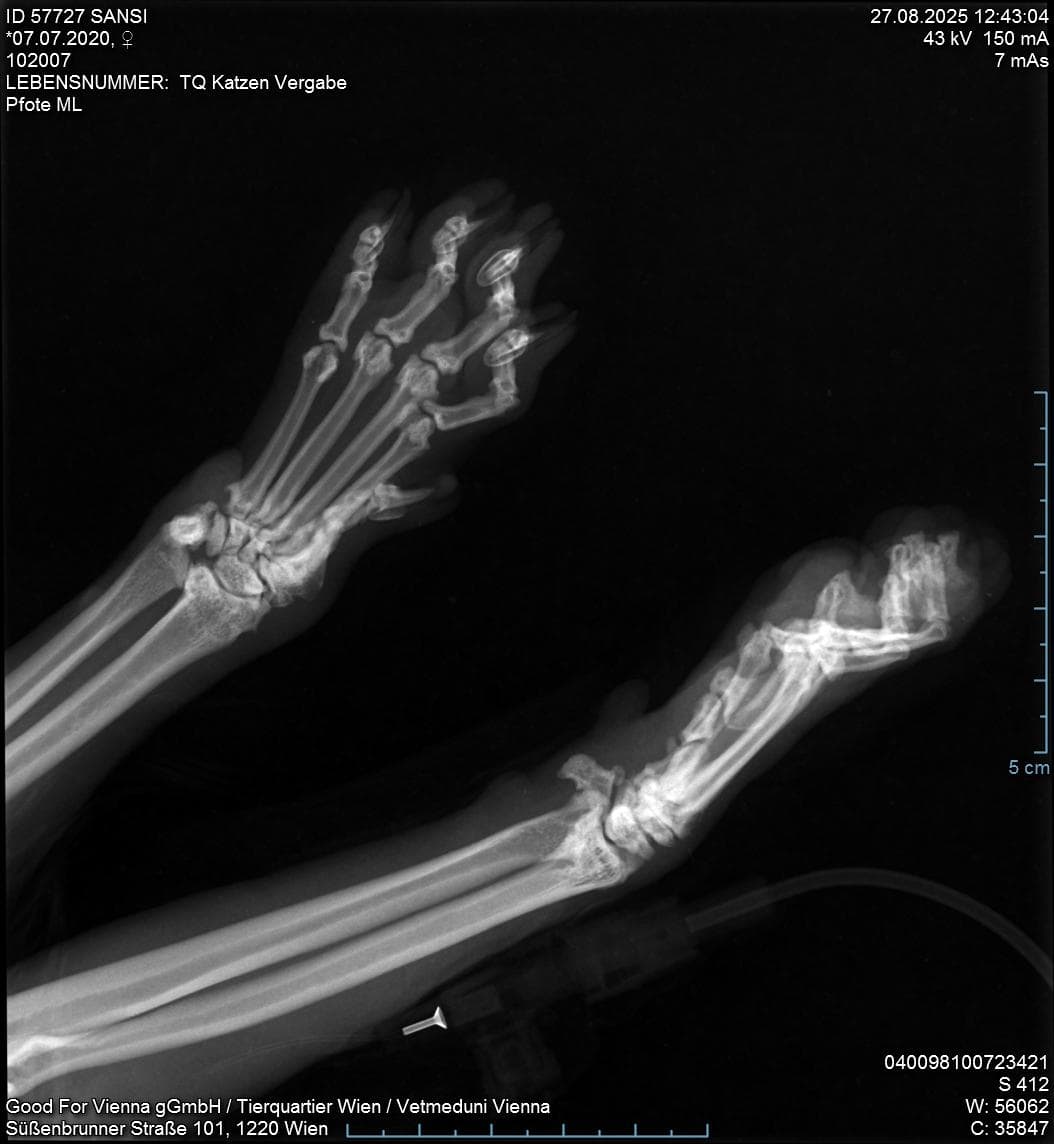

“Die Erfahrung unserer Tierärzteschaft zeigt, dass vielen Menschen die gesundheitlichen Problematiken dieser Rasse noch immer nicht bewusst sind”, erklärt Manfred Hochleithner, Präsident der Landesstelle Wien der Österreichischen Tierärztekammer. “Die Faltohren entstehen durch eine genetische Mutation, die zu Knochen- und Knorpelfehlbildungen führt, bekannt als Osteochondrodysplasie. Diese Fehlentwicklung betrifft das gesamte Skelett, nicht nur die Ohren.”

Die Scottish Fold Katzen zeigen infolgedessen ein verändertes Gangbild mit Lahmheiten, sie vermeiden es zu springen und wirken oft besonders ruhig – ein Verhalten, das fälschlicherweise als Gelassenheit interpretiert wird. Häuig kommen geschwollene Gelenke an den Vorder- und Hinterbeinen hinzu. Das Zeitpunkt des Auftretens und die Ausprägung der Symptome sind unterschiedlich, jedoch sind alle Katzen dieser Rasse davon betroffen. Hochleithner mahnt: “Katzenbesitzer*innen übersehen leichte Symptome jedoch häufig und sind dann beim Tierarztbesuch ganz überrascht von der Diagnose und den damit einhergehenden Kosten für die Dauerbehandlung ihres Tieres. Eine Heilung ist nicht möglich. Manchmal sind Tierärzt*innen sogar gezwungen noch sehr junge Katzen aufgrund der schwerwiegenden Veränderungen und der damit einhergehenden Schmerzen und Bewegungseinschränkungen zu euthansieren.”

Röntgenbild der deformierten Pfoten einer Scottish Fold